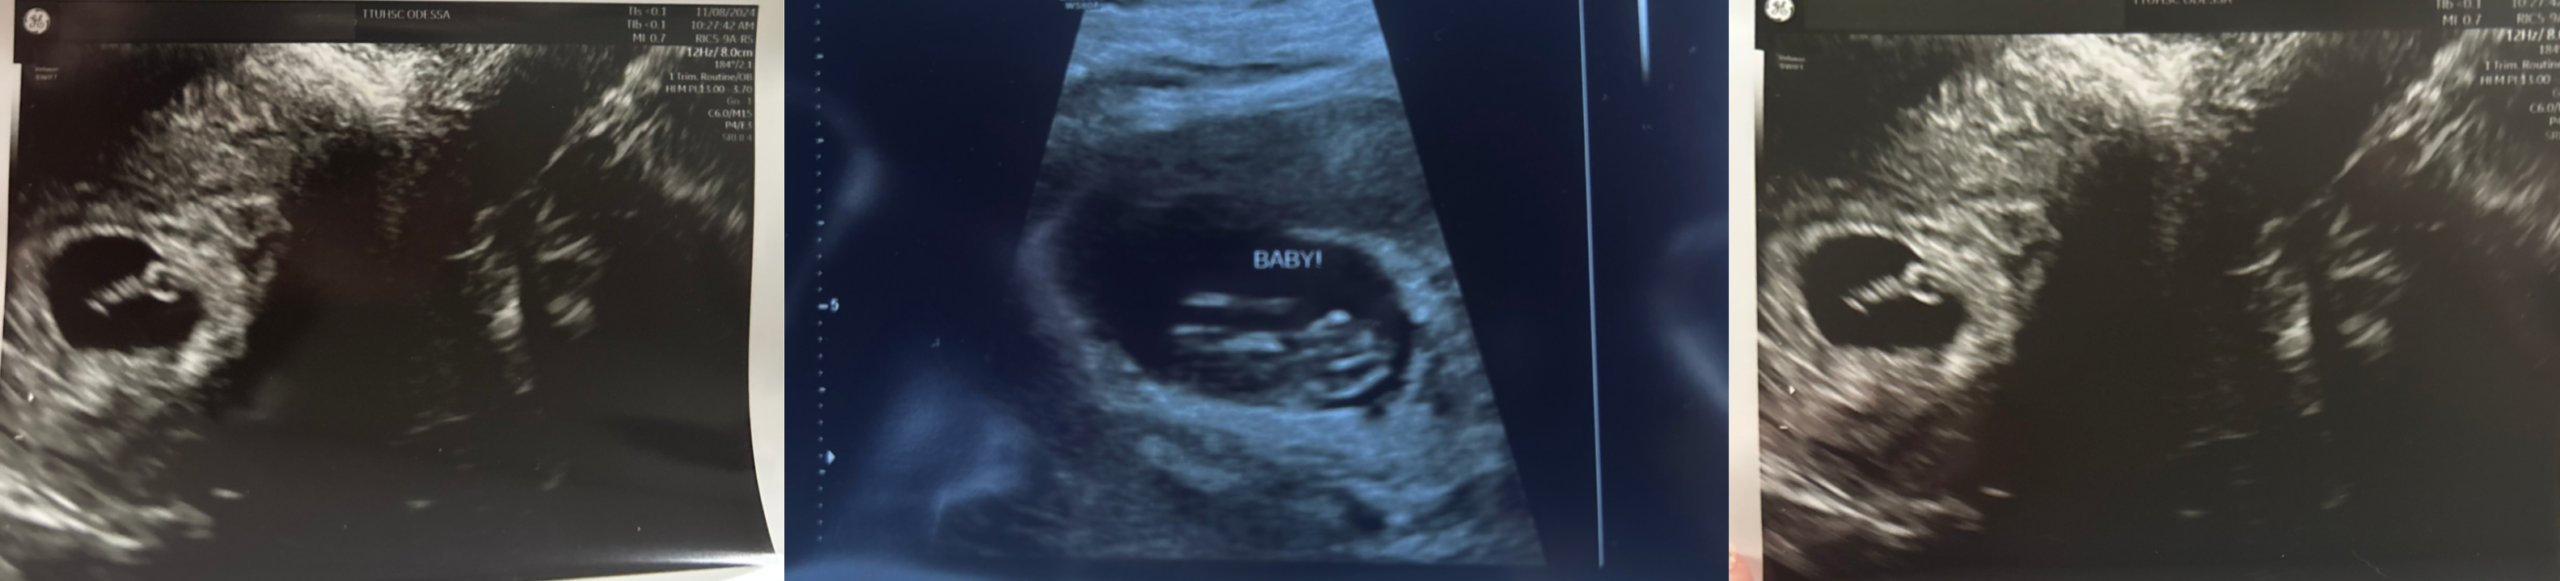

*** WE ARE HAVING A BABY SHOWER ***

We have been wanting an addition to our family for so long. When we found out about baby Johnny, it felt like our

prayers had been answered. We are so excited to welcome him home!

Counting Down

to Baby Johnny